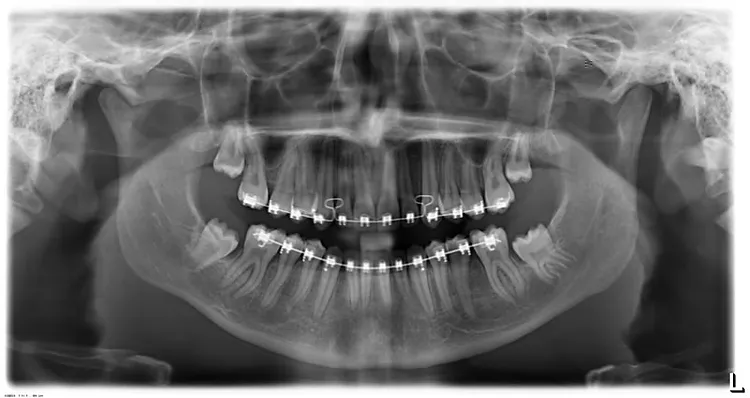

In this case the wisdom teeth were intentionally retained so that healthy molar teeth could be brought into position after extraction(removal) of four decayed molar teeth. Before and after.

Before